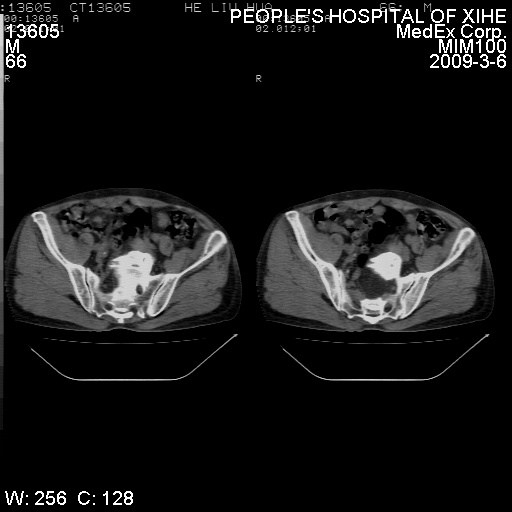

标题: CT18522:男,66岁。考虑结核有错吗 [打印本页]

标题: CT18522:男,66岁。考虑结核有错吗

x线片示:骶骨密度增高。

考虑----腰椎骶化-----退变-----椎管狭窄

腰骶椎退行性改变。

腰骶椎退行性改变,建议重建看看!

退行性变,椎体滑脱

腰椎滑脱并有退变

退行性变,椎体滑脱。建议同椎体平行进一步扫描。